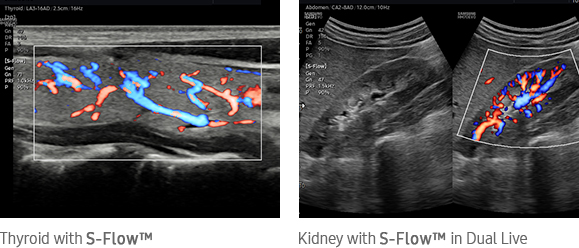

Directional power Doppler to examine peripheral vessels

The function uses directional power Doppler technology, enabling you to examine even the peripheral vessels. It displays information on the intensity and direction of blood flow.

Kidney with S-Flow™ in Dual Live